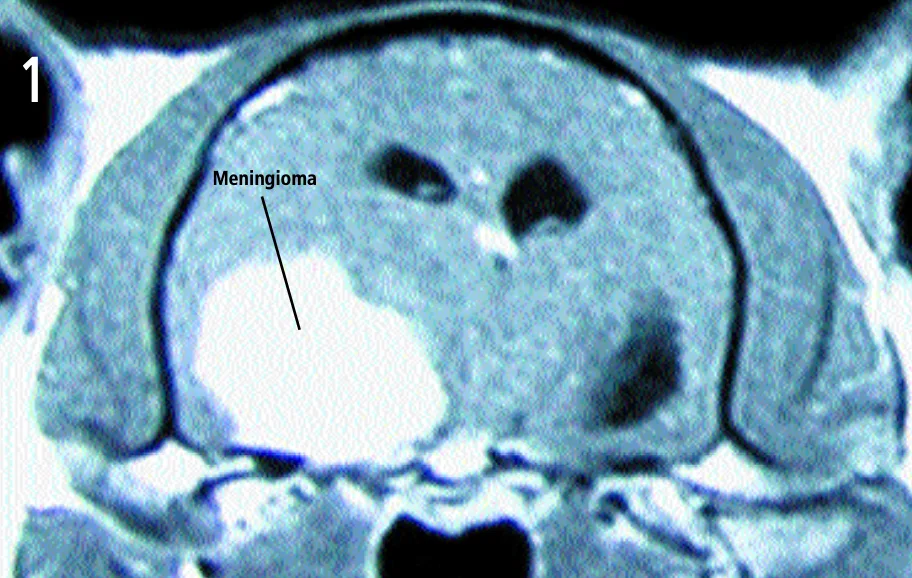

Transaxial view—T1-weighted, contrast-enhanced magnetic resonance image

A large, left-sided cerebral mass, evident on both images.

The mass is uniformly contrast-enhancing on the MRI, appears to have a broad-based attachment to the skull, and has distinct margins-all of which are characteristic of intracranial meningiomas. The most likely diagnosis is meningioma. A smaller, right-sided mass can be seen on the dorsal image. This mass also has characteristic features of meningioma. Both masses were removed and confirmed histologically as meningiomas. The cat made a full recovery.

Transaxial view—T1-weighted, contrast-enhanced magnetic resonance image